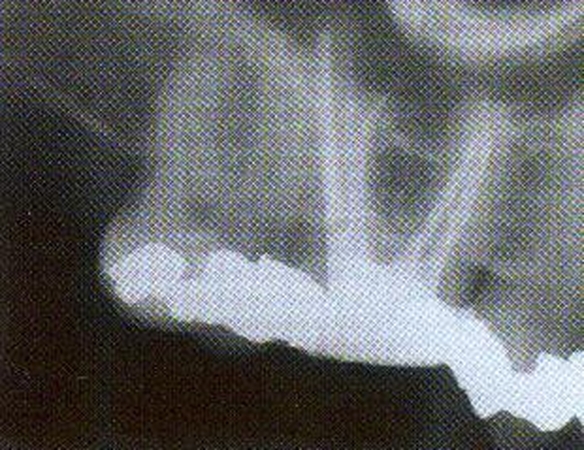

Endodontologo kabinetas — Dainavos poliklinikoje